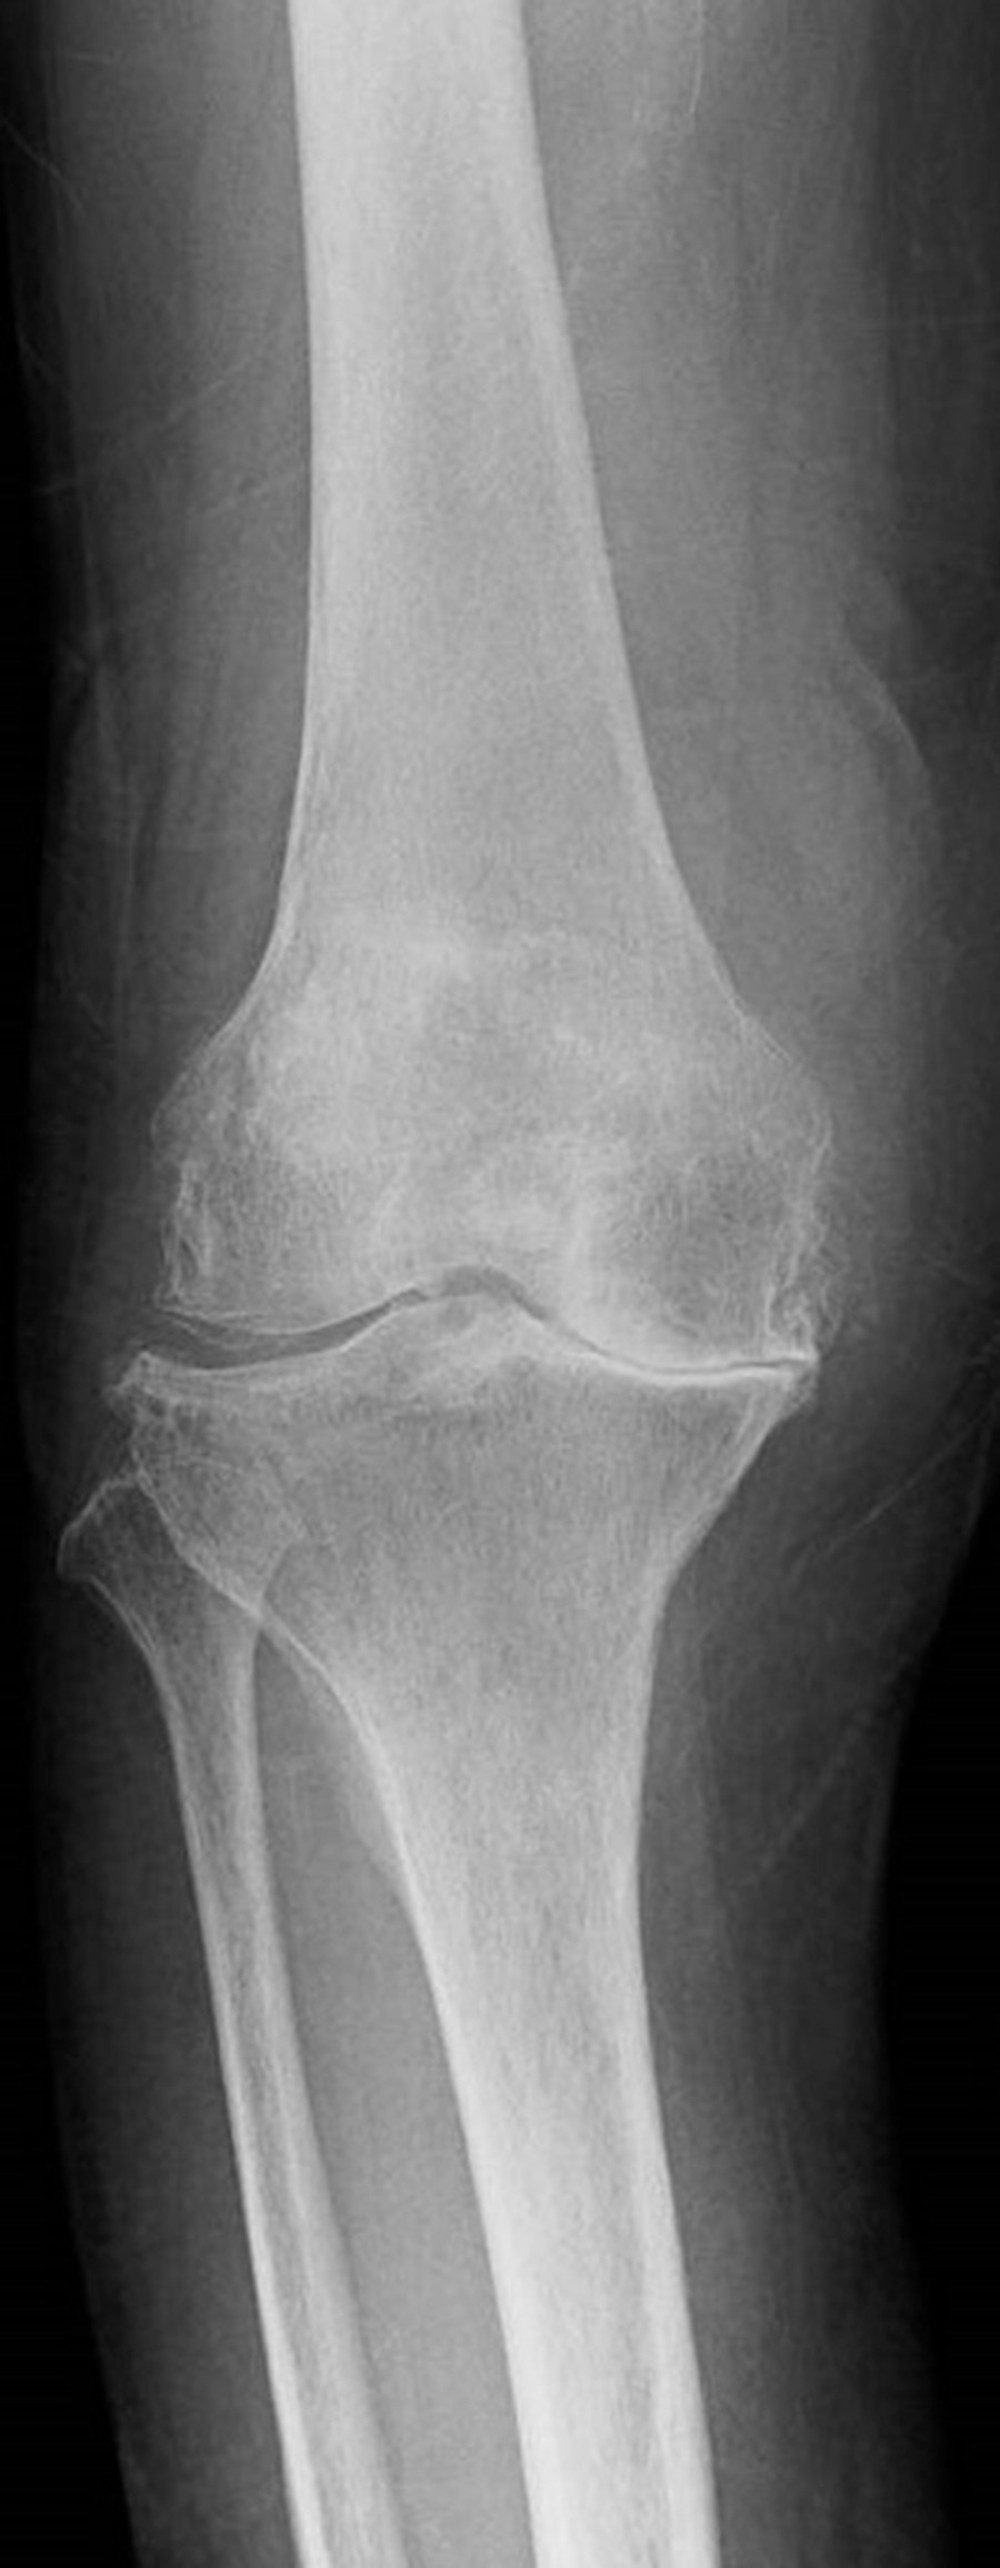

plain x ray on knee joint showing joint space narrowing and Subchondral What Is Compartment Narrowing medial joint space narrowing means that you have osteoarthritis on the inner side of your knee. The term early osteoarthritis of the knee has been proposed and has been defined as meeting three main criteria 9: joint space narrowing (jsn) refers to the space between the bones in a person's joints. In the knee, joint space narrowing has. What Is Compartment Narrowing.

AP and lateral radiographs demonstrate mild medial joint line narrowing What Is Compartment Narrowing joint space narrowing (jsn) refers to the space between the bones in a person's joints. narrowing joint space indicates cartilage loss and worsening osteoarthritis. In the knee, joint space narrowing has been linked to loss of. The term early osteoarthritis of the knee has been proposed and has been defined as meeting three main criteria 9: medial. What Is Compartment Narrowing.